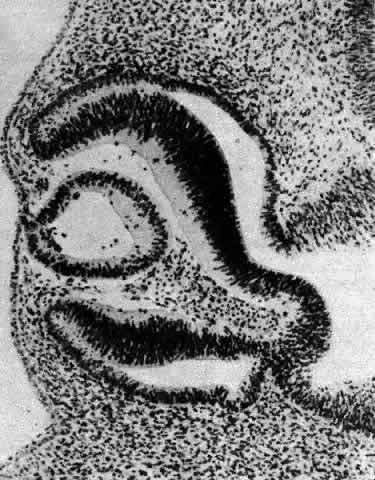

Other opacities that fall under the category of capsulolenticular cataracts are the polar cataracts. In this case, the opacities are situated at either pole of the lens and generally involve only the superficial cortical area. The relatively common anterior variety assumes a number of forms but is typically plaquelike and circumscribed. The size of the opacity may vary from a small dot to one that occupies the entire pupillary region. Because it may have a laminate appearance, it has also been called a pyramidal cataract. Similar opacities are observed in children who have had corneal ulcers during infancy. The fact that the fetal nucleus of the lens is not involved suggests an occurrence relatively late in intrauterine life. Occasionally, an opacity might be seen above the previously incurred derangement separated by an apparently normal lenticular zone, producing the so-called reduplicated cataract. In this case, it is believed that, following an initial disturbance, normal fibers are deposited, followed later by a new, sometimes more severe disturbance that produces a second region of opacification. There are a number of variations on this theme, and such opacities may assume myriad possible forms. It may be significant that these opacities are often associated with a strand or strands of pupillary membrane that bridge the iris (in the region of the collarette) to the polar cataract.181–183 Similar adhesions to the pupillary margin have been noted. Another observation has been that these cataracts are often associated with signs of keratitis, most notably corneal opacification. It is interesting that, histologically, the changes are similar to those observed in the adult human lens following corneal ulceration.177–180 The polar cataract is typically associated with a hyperplasia of the epithelium and a great deal of necrosis of lens fibers in the subepithelial area.184 Multistratification of the epithelium occurs as the cells fill a depression left by the necrotic fibers (Figs. 36 AND 37). The cells become spindle-shaped and produce PAS-positive material. Contrary to a long-held but erroneous notion, the plaque thus formed does not represent a metaplastic transformation of epithelial cells into fibroblasts.185 The plaque is often undermined by normal cuboidal epithelial cells and is eventually surrounded by capsulelike material (see Figs. 36 AND 37). The most reasonable explanation of the basis of this anomaly is the development of intrauterine inflammation. Although it has been suggested that the anterior polar cataract may be the result of a persistent vascular tunic that interferes with nutrition, the counterpart, the posterior polar cataract, need not be associated with hyaloid remnants, yet the histologic picture is quite similar.

Fig. 36. Photomicrographs of the development of anterior subcapsular cataract. A. The beginning of multistratification of the anterior epithelium, owing to localized hyperplasia of the lens epithelial cells. B. Further stratification of the epithelium, with denucleation occurring in some of the cells. C. The final stage of cataract formation showing the so-called fibrous plaque (F), bounded on the anterior and posterior sides with capsule material. Beneath the posterior capsule (C) a newly formed epithelial population can be seen (E). (Yanoff M, Fine BS: Ocular Pathology. New York, Harper & Row, 1975)

Fig. 37. Development of anterior polar cataract: schematic illustration of the sequence of events described in Figure 36. (Font RI, Brownstein S: A light and electron microscopic study of anterior subcapsular cataracts. Am J Ophthalmol 78:972, 1974)